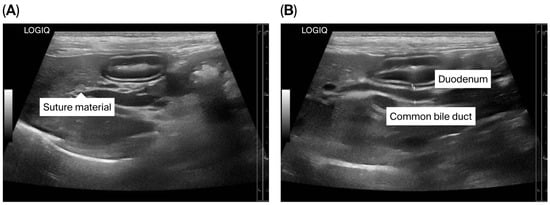

Congenital umbilicobiliary fistula is a rare disease reported in humans and dogs. A 2-month-old, intact, male French Bulldog presented with a greenish-yellow discharge dripping from the umbilicus since birth. Complete blood count and serum biochemistry were within normal limits, but serum alkaline phosphatase [...] Read more.

Congenital umbilicobiliary fistula is a rare disease reported in humans and dogs. A 2-month-old, intact, male French Bulldog presented with a greenish-yellow discharge dripping from the umbilicus since birth. Complete blood count and serum biochemistry were within normal limits, but serum alkaline phosphatase activity was mildly elevated. A positive contrast cystogram was performed to rule out a patent urachus and confirmed the presence of a vesicourachal diverticula, a type of urachal anomalies. An abdominal ultrasound and computed tomography fistulogram demonstrated a communication between the umbilicus and common bile duct, which suggested an umbilicobiliary fistula. Surgical correction of the umbilicobiliary fistula and vesicourachal diverticula was successfully performed with an uneventful recovery. Histological analysis of the fistulous tract demonstrated a cuboidal/columnar lining epithelium that transitioned to squamous epithelium near the umbilicus. Agenesis of the gallbladder was noted. The application of multiple imaging techniques in the diagnosis and surgical correction of these congenital abnormalities (umbilicobiliary fistula, gallbladder agenesis, and vesicourachal diverticula) was beneficial for treatment planning and outcome. Full article